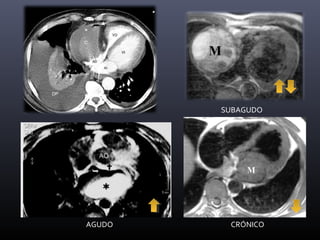

Hematoma

• RM preferible a TC

T1 T2 OTROS

AGUDO  

SUBAGUDO   HETEROGENEO

CRÓNICO   BORDE

PERIFERICO

(Ca/Hemosiderina)

-Neoplasias

SUBAGUDO

CRÓNICOAGUDO